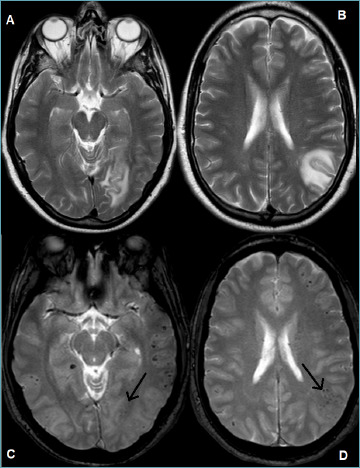

Primary angiitis of the central nervous system (CNS) is an uncommon inflammatory disorder, with highly variable clinical presentation. It needs to be differentiated from several mimickers, such as CNS involvement in systemic vasculitides, connective tissue disorders, infectious disease, and leukodystrophy as well as neoplastic diseases. The diagnosis requires a combination of clinical and laboratory investigations, multimodal imaging, and histopathological examination, which should be available for confirmation. In the present paper, the histopathological features of primary angiitis of the CNS are described and highlighted to help pathologists avoid misdiagnosis of a treatable acquired disease.

Abstract Image